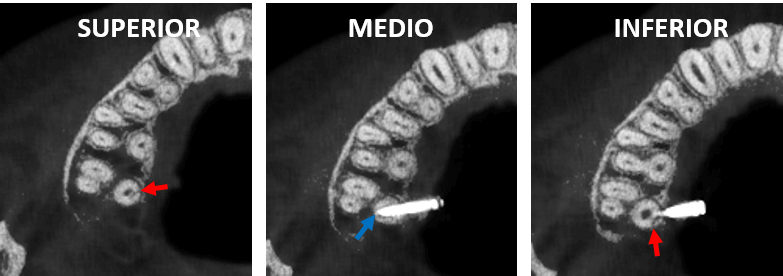

En cortes sagitales (Fig.4) se observa el dispositivo de fijación quirúrgica (flechas azules) comprometiendo el conducto radicular de la raíz palatina, donde también se observan los trazos de fractura (flechas rojas) en sentido superior e inferior en relación con la perforación del material hiperdenso.